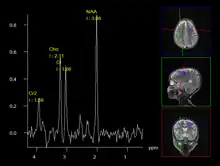

A less intrusive alternative imaging technique is magnetic resonance spectroscopy (MRS), which is used to determine the chemical compositions of cells. However, it is not as reliable as biopsies.[12]